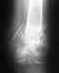

Re: Сроки реабилитации после остеосинтеза при переломе лодыжки

Нет единого универсального срока прекращения иммобилизации после остеосинтеза. В каких-то случаях вообще гипс не накладывают, иногда до снятия швов, в какких-то случаях на более длительный период. Это обусловлено конкретным видом перелома и сопутствующих повреждений связок, а также особенностями остеосинтеза в конкретном случае. Так что вопрос о длительности иммобилизации целесообразно задавать врачу, делавшему операцию и накладывавшему гипс - он в курсе всех обстоятельств.